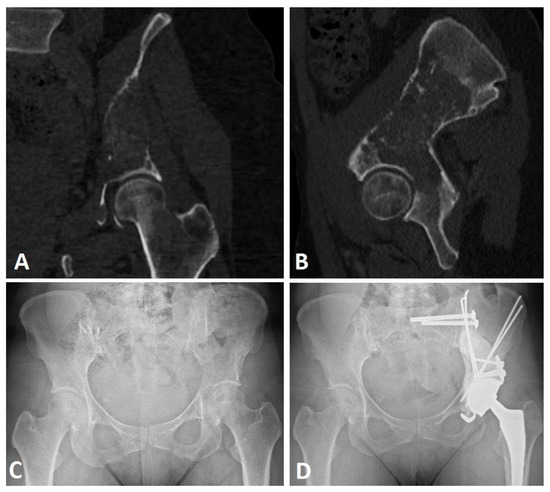

2.2. Extensive Acetabular Bone Loss Management

2.2.1. Treatment Strategy

2.2.2. Surgical Procedure

| Harrington Grade | Grade 2 | 8 (32.3%) | |

| Grade 3 | 14 (66.7%) | ||